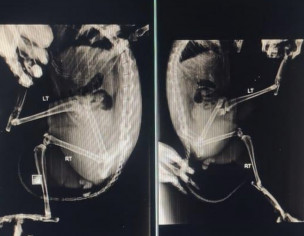

My cat fell from height and broke his bone. He also got external injury due to which he lost a lot of blood. Due to blood loss I dont think at this stage he can bear surgery or is eating fine but he struggles a lot to walk. SpeciallyI don’t want any risk for his life. What should I do please guide.

Attach Photo here: